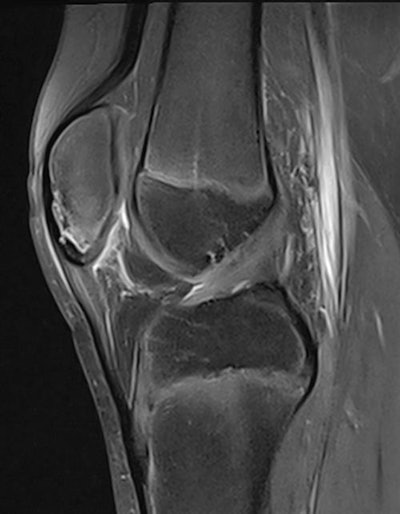

I have worked a lot with hip, knee, and ankle imaging, especially MRI. Injury to the cruciate ligaments, posteromedial and posterolateral corner of the knee has been a special interest, as well as injuries around the ankle. However, the spectrum of sports injuries covers all joints, both upper and lower limb, and every day there is a new challenge and something new to learn.

Imaging can detect both subtle and obvious injuries associated with sporting activity. Early stress reactions in bone, tendons, and soft tissues can be seen, as well as all sorts of ruptures and fractures. However, some injuries are subtle, and if you don't look for them, you will not find them. A sports radiologist must look for smaller changes than other radiologists are used to. This may be because the athlete is imaged very early after an injury or after the start of a complaint, and smaller injuries may be more important in an athlete than in other patients.